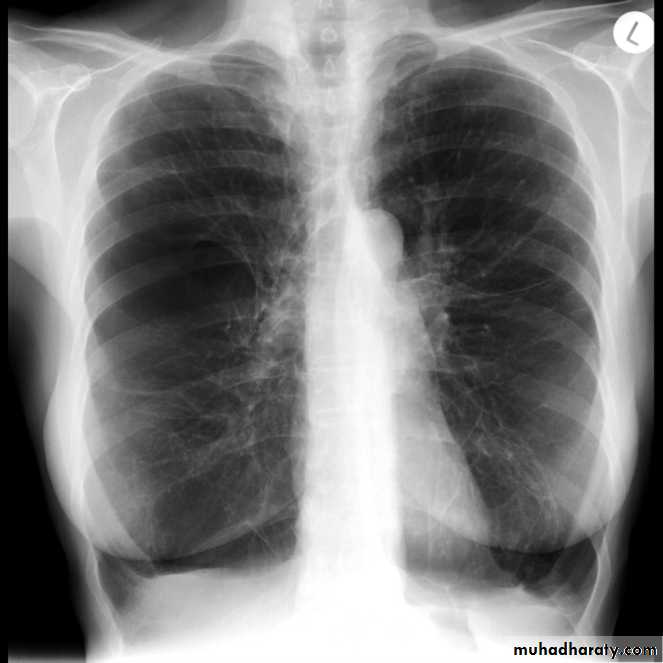

A tension pneumothorax

A tension pneumothorax occurs when intrapleural air accumulates progressively in such a way as to exert positive pressure on mediastinal and intrathoracic structures. It is a life threatening occurrence requiring rapid recognition and treatment is required if cardiorespiratory arrest is to be avoided.Radiographic features

A pneumothorax will have the same features as a run-of-the-mill pneumothorax with a number of additional features, helpful in identifying tension. These additional signs indicate over expansion of the hemithorax:

ipsilateral increased intercostal spaces

shift of the mediastinum to the contralateral side

depression of the HYPERLINK "http://radiopaedia.org/articles/diaphragm" hemidiaphragm